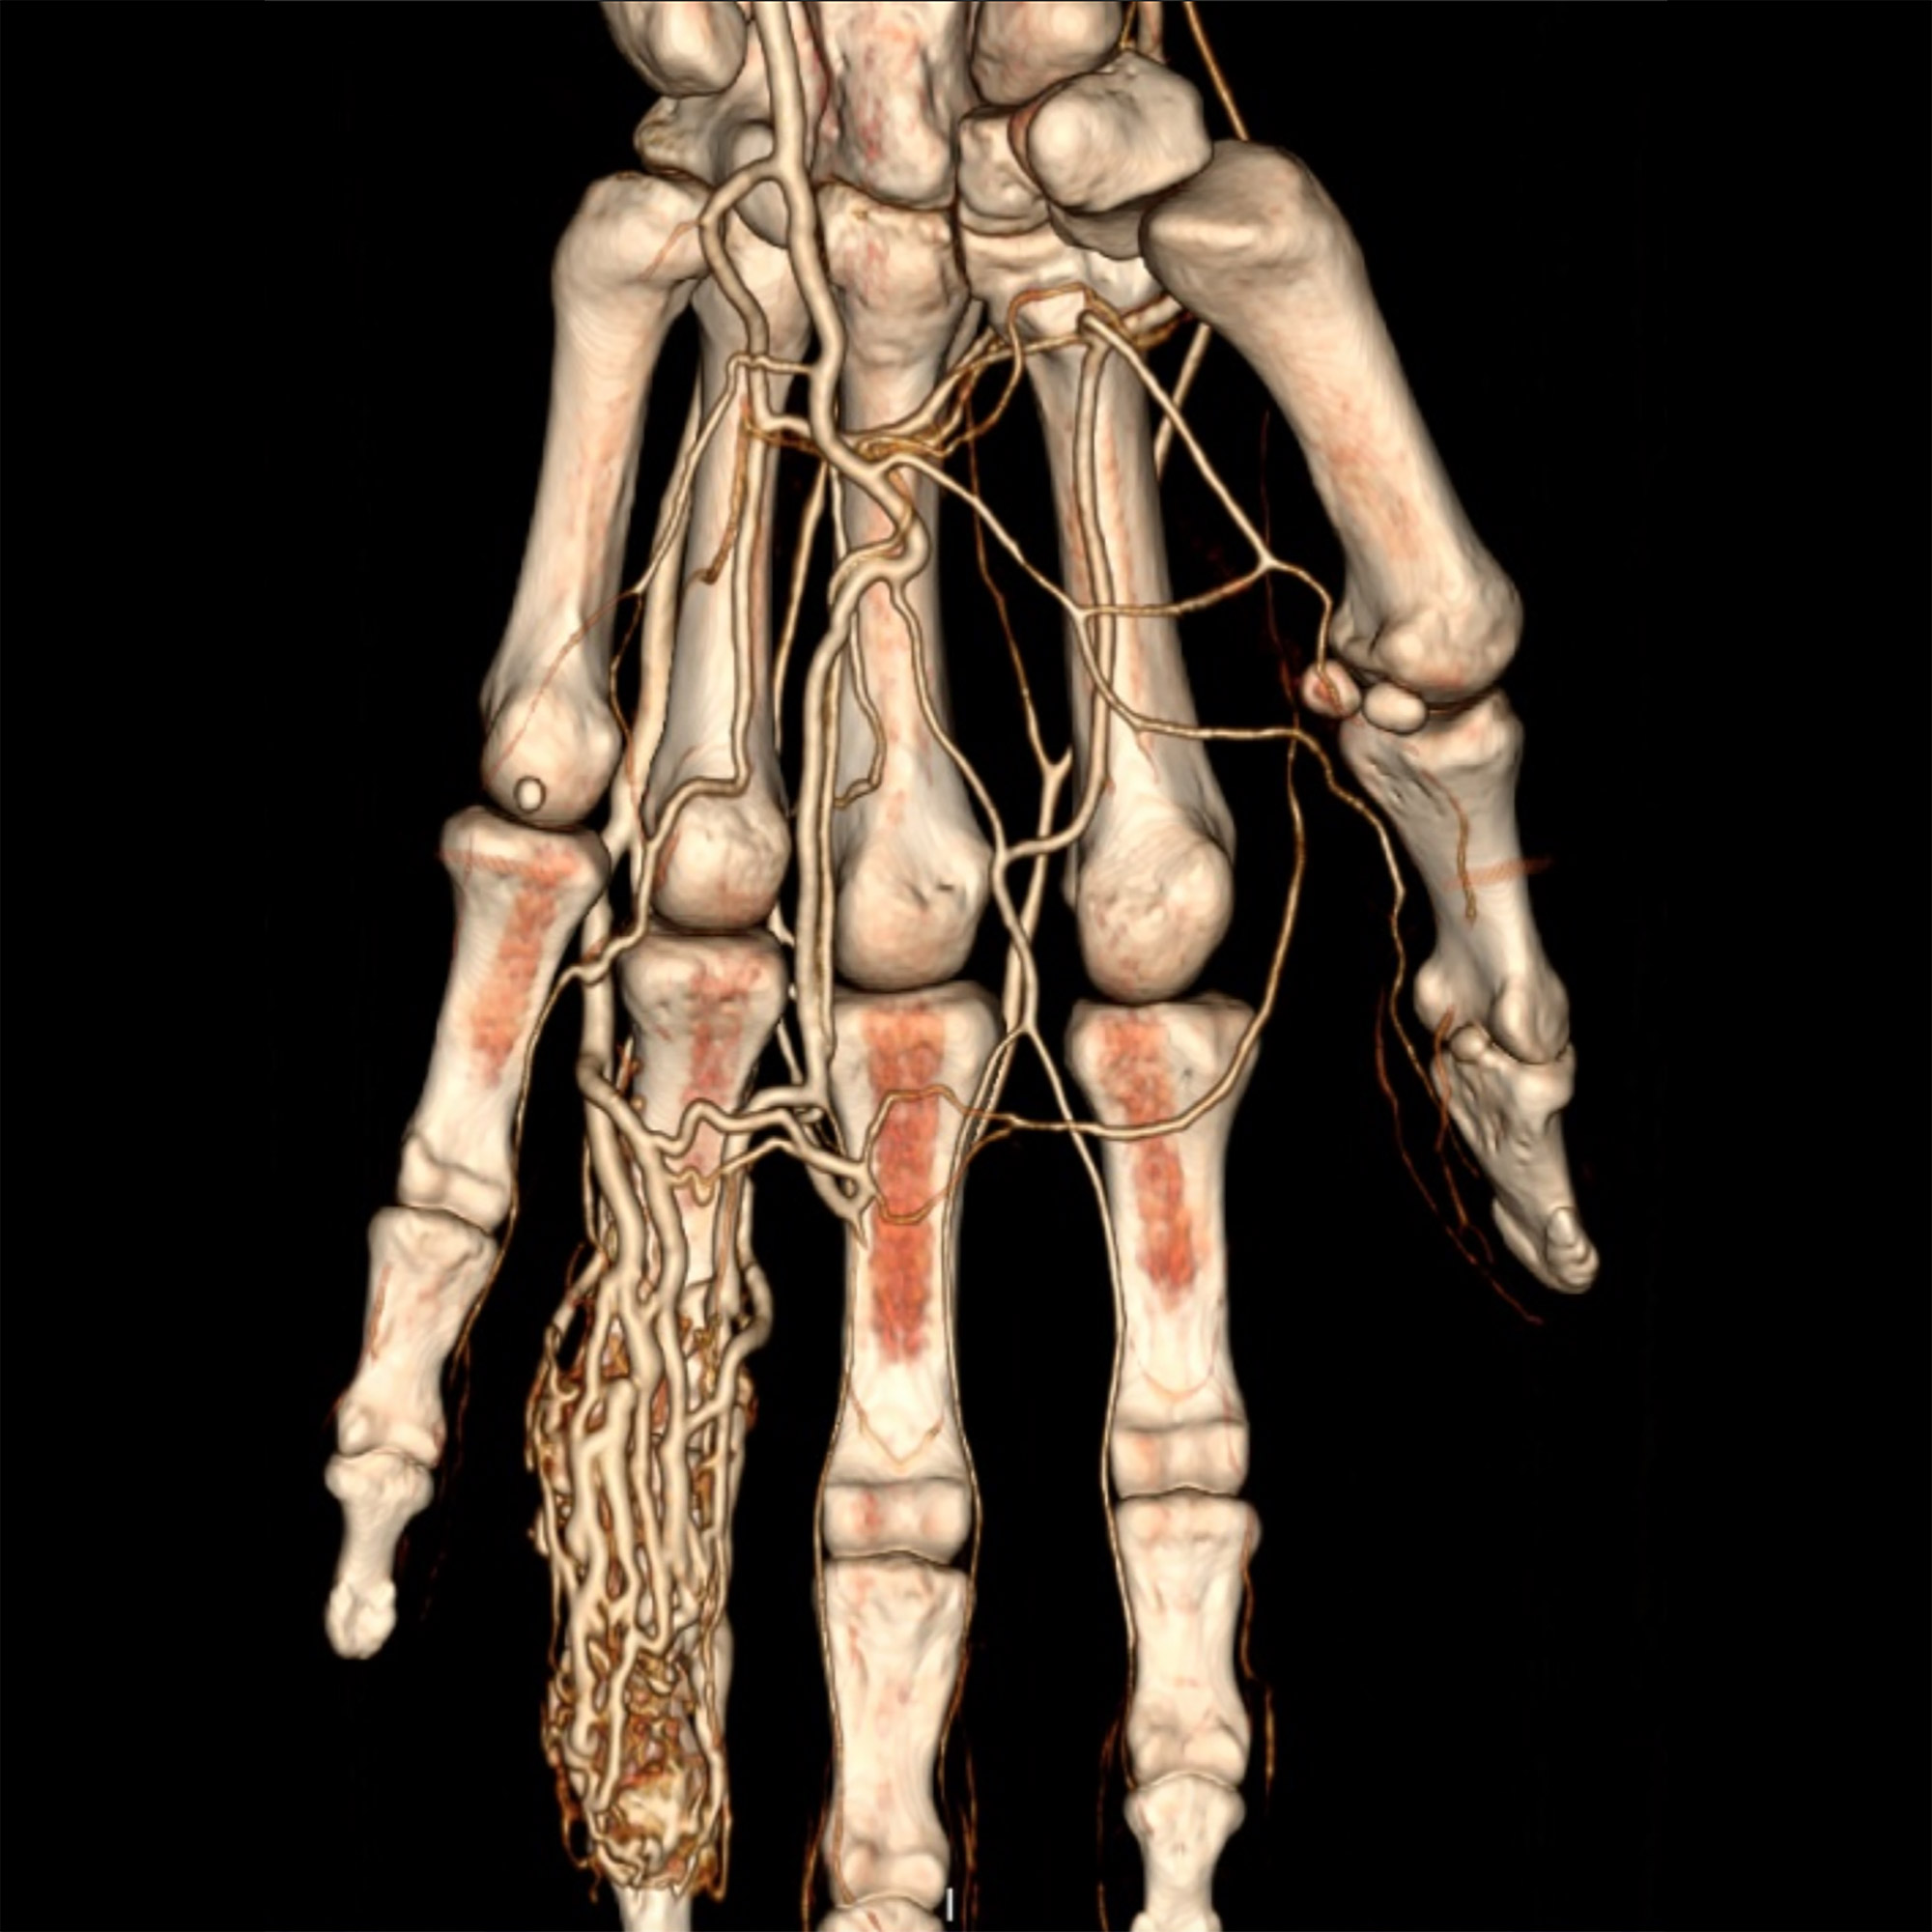

Le scanner, aussi appelé tomodensitométrie (TDM), est un examen d’imagerie médicale qui utilise les rayons X pour obtenir des images très détaillées du corps humain. Contrairement à une radiographie classique, le scanner réalise des images en coupes, comme des « tranches », permettant d'explorer avec précision une région du corps dans les trois plans de l’espace, voire en 3D.

• une visualisation précise des organes, os, vaisseaux ou poumons ;

Une fois les images réalisées, elles sont analysées par un radiologue qui interprète les résultats. Des reconstructions 3D ou volumiques peuvent être effectuées si besoin.